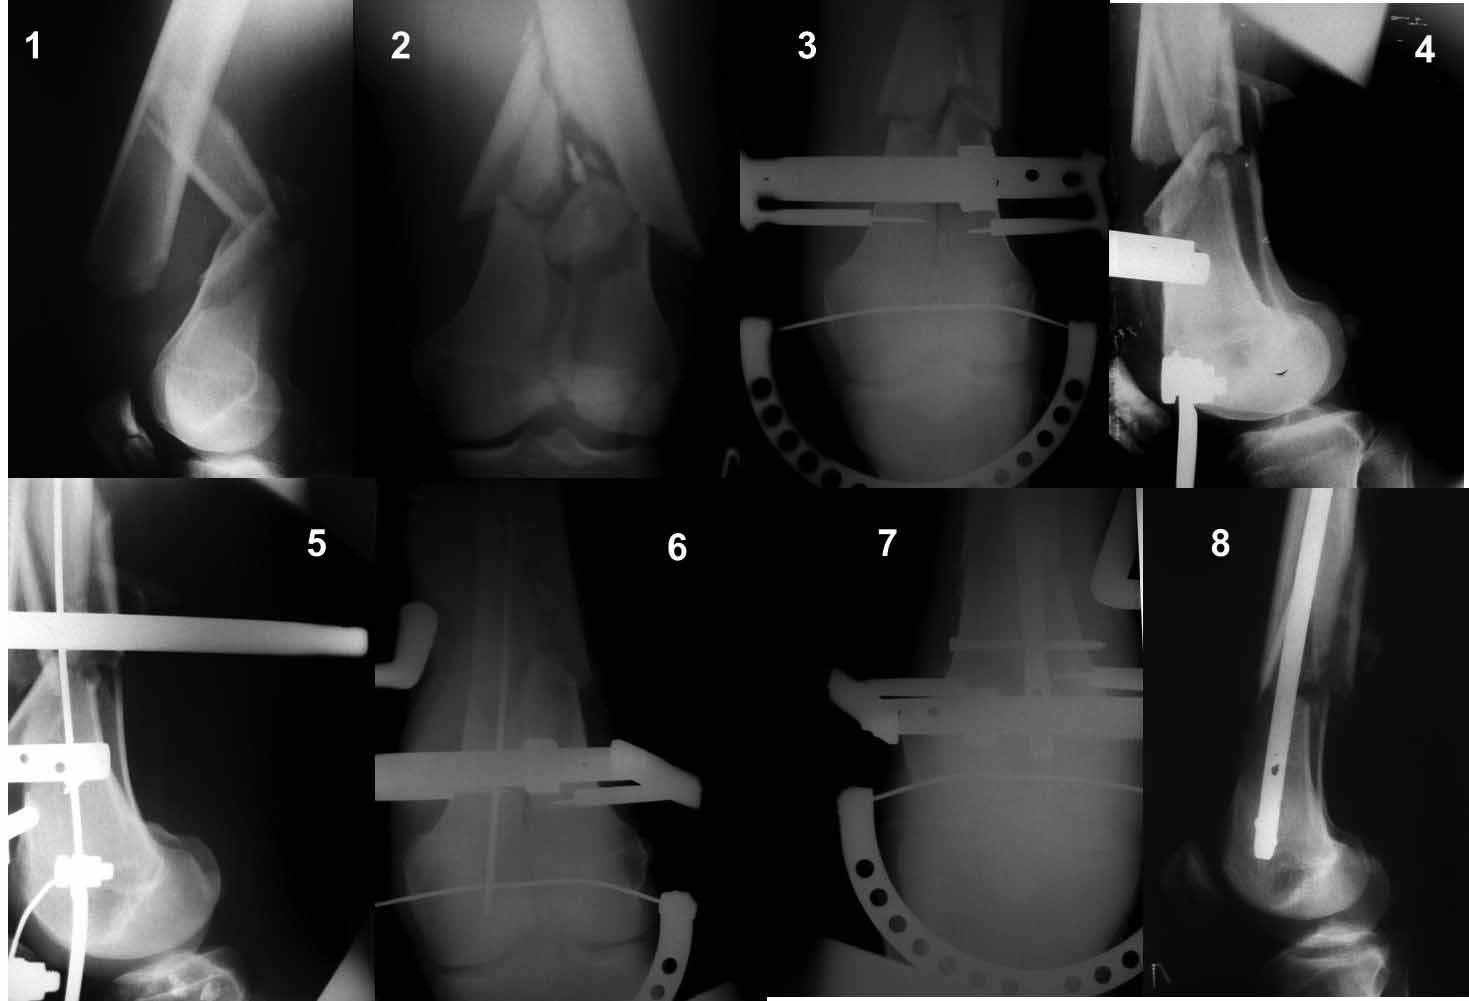

Re: перелом бедра

Переломы не слишком низкие для LCP и ретроградного стержня?

Нет, не слишком. Самый раз!

внутреннего мыщелка придется делать дополнительный разрез медиально, не так ли?

Нет, не так.

Как? посмотрите здесь:

:-) Опять забыли самый лучший вариант - антеградный остеосинтез...

Ну зачем же так. Всё-таки считается "золотым стандартом". Во вложенном файле коллаж из сохранившихся фотографий одной из операций. Всё сделано закрыто и без ЭОПа.